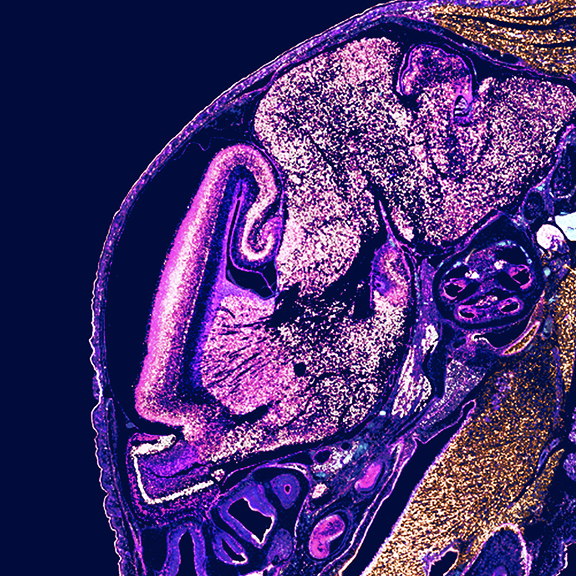

Researchers used the Visium HD assay in human colorectal cancer FFPE samples to identify spatially distinct immune cell populations in and around the tumor. They then validated their findings, and identified an anti-tumor macrophage niche, with the Xenium platform.

High-definition spatial transcriptomic profiling of immune cell populations in colorectal cancer